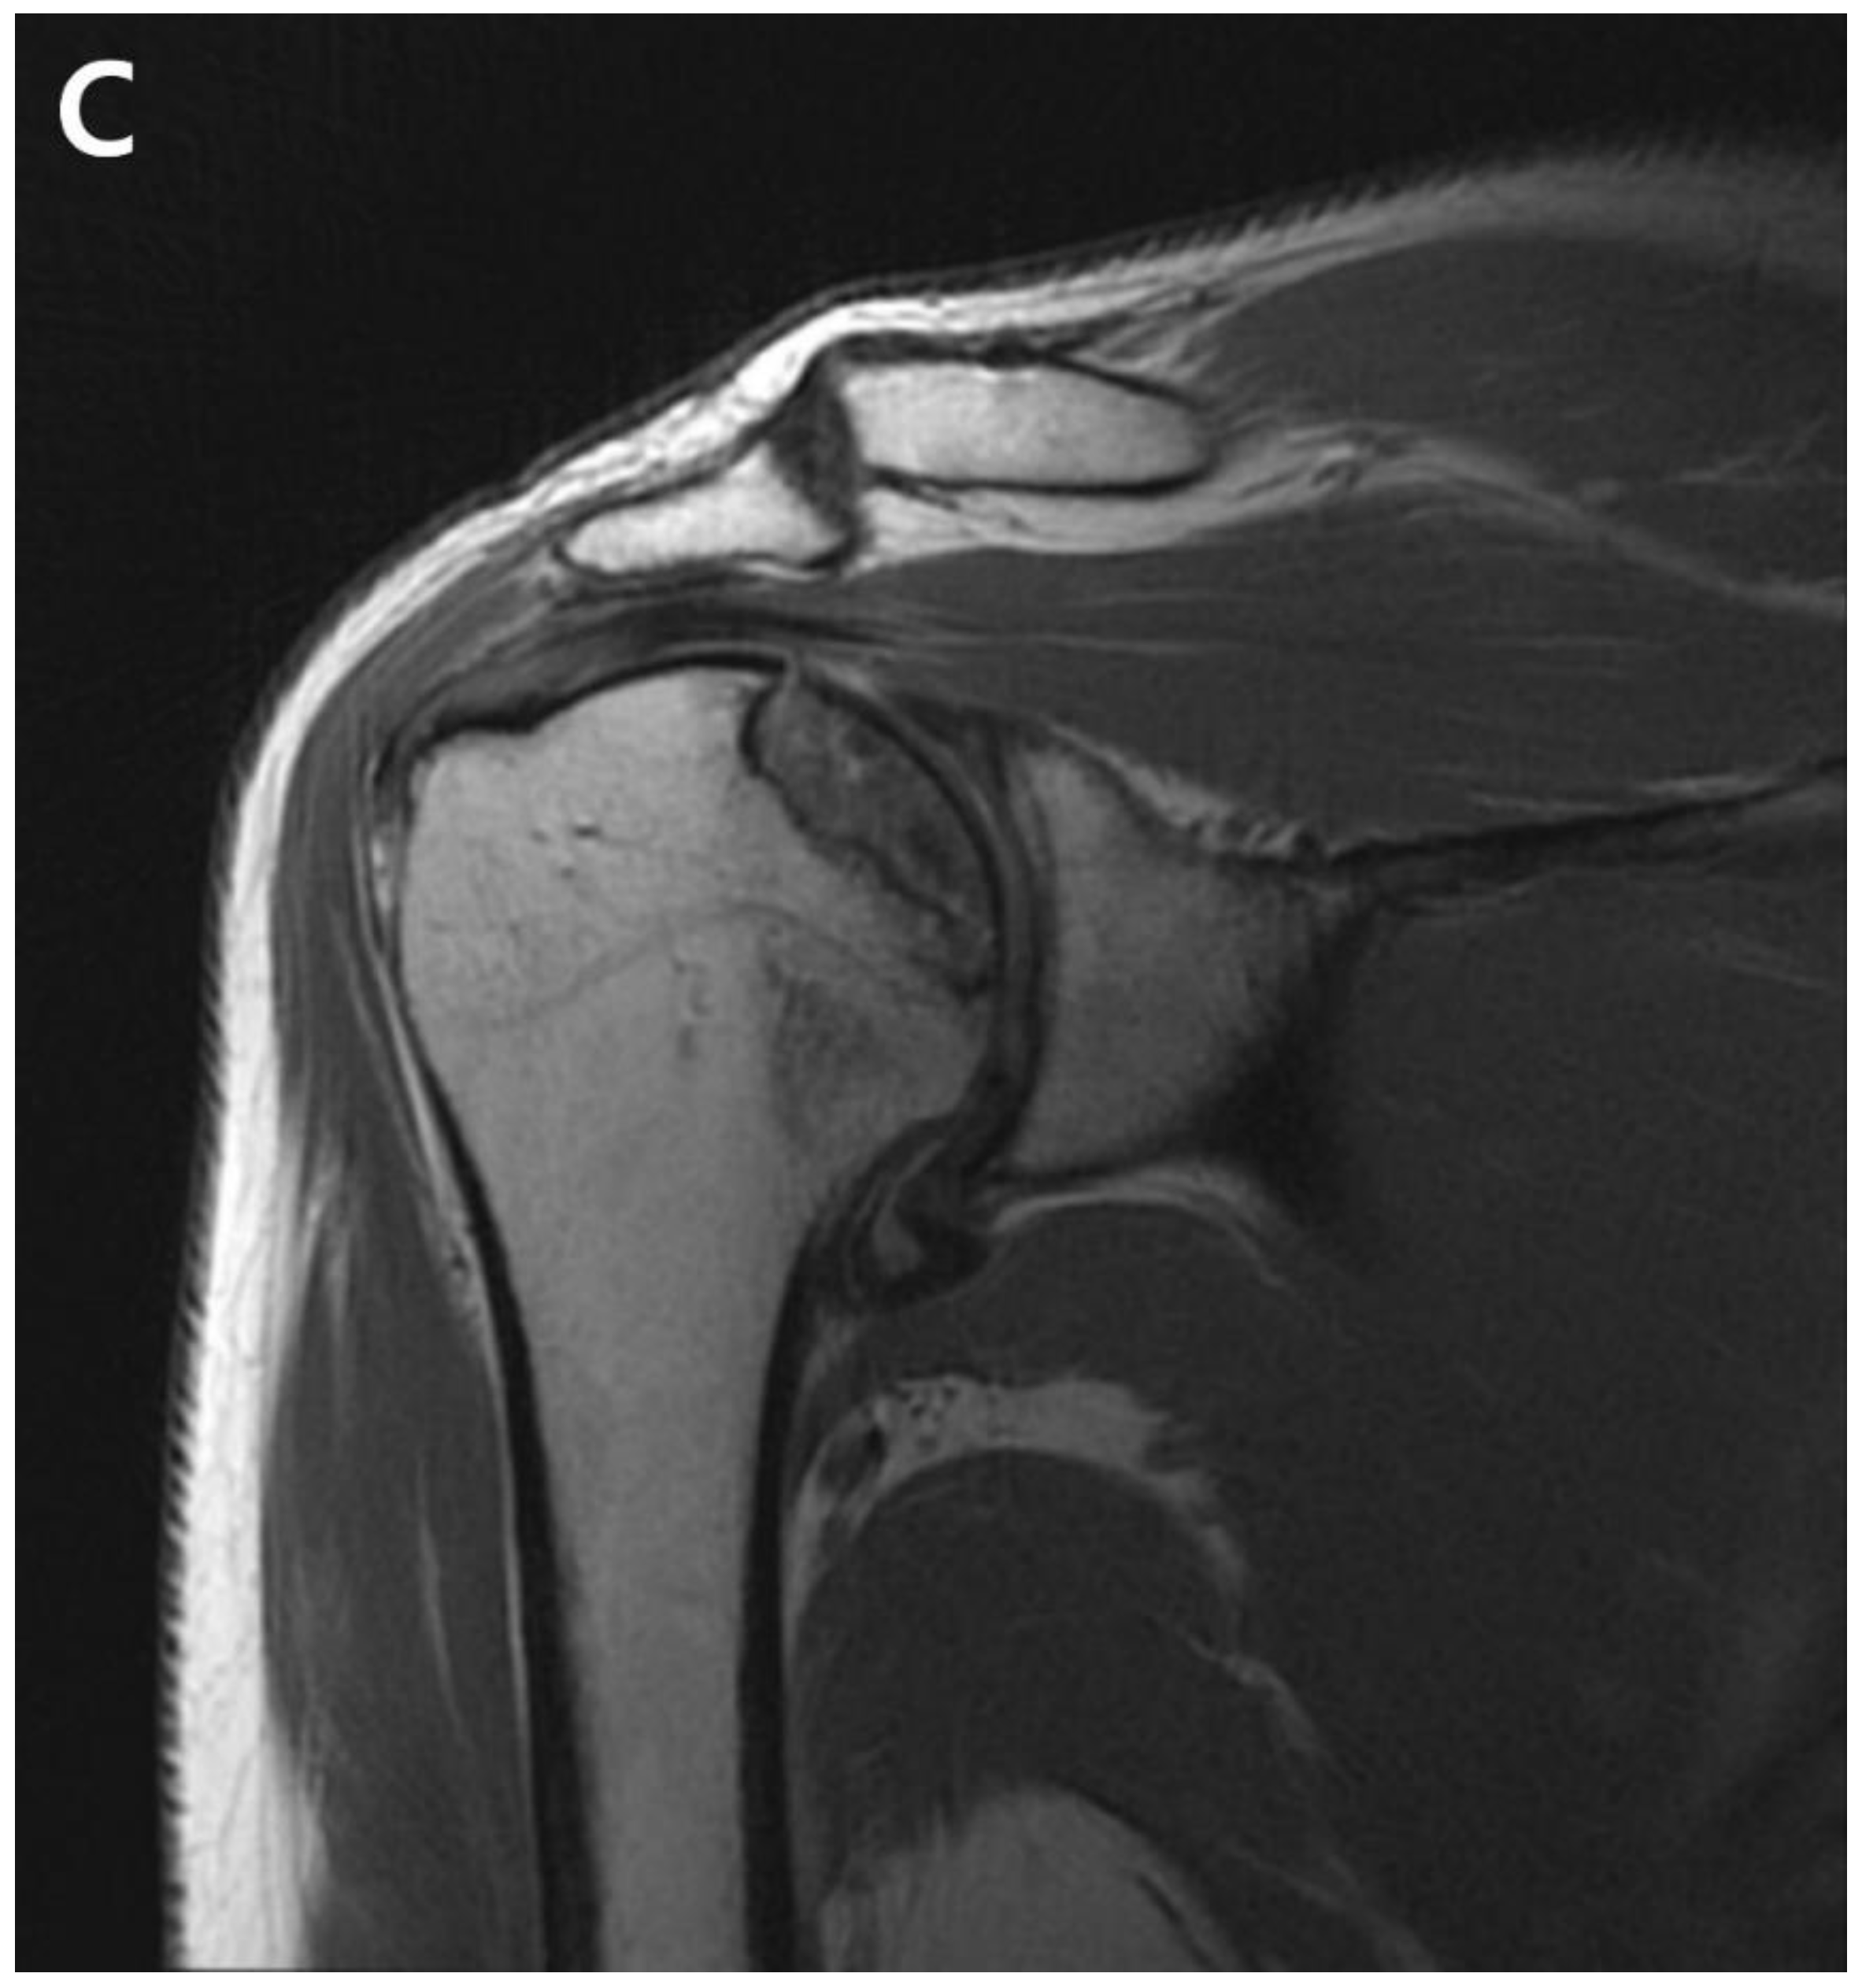

The patient returned to the hospital 21 months after the ACR with right shoulder pain. Plain shoulder anteroposterior radiography and MRI showed a subchondral cyst and a high bone marrow signal on the epiphysis of the superomedial area of the humeral head on T2-weighted images, suggesting avascular osteonecrosis of Cruess stage II (Fig. 4). The patient denied any traumatic injury, radiotherapy, exacerbation of chronic hepatitis, alcohol consumption, or use of other medications. The patient received six intra-articular injections of glucocorticoids during the 15 months of open follow-up at another institution. It is unclear whether the six intra-articular injections were corticosteroids. At 3-years postoperatively, his VAS score was 3, ASES score was 63, and CMS score was 59, indicating increased discomfort. As the patient found the discomfort tolerable in terms of both work capacity and activities of daily living, we decided to maintain the current status and continue observation until osteonecrosis progressed (Fig. 5.)

Figure 5. Anteroposterior radiograph of the shoulder shows articular collapse on the superomedial side of the humeral head at 3-years postoperatively.